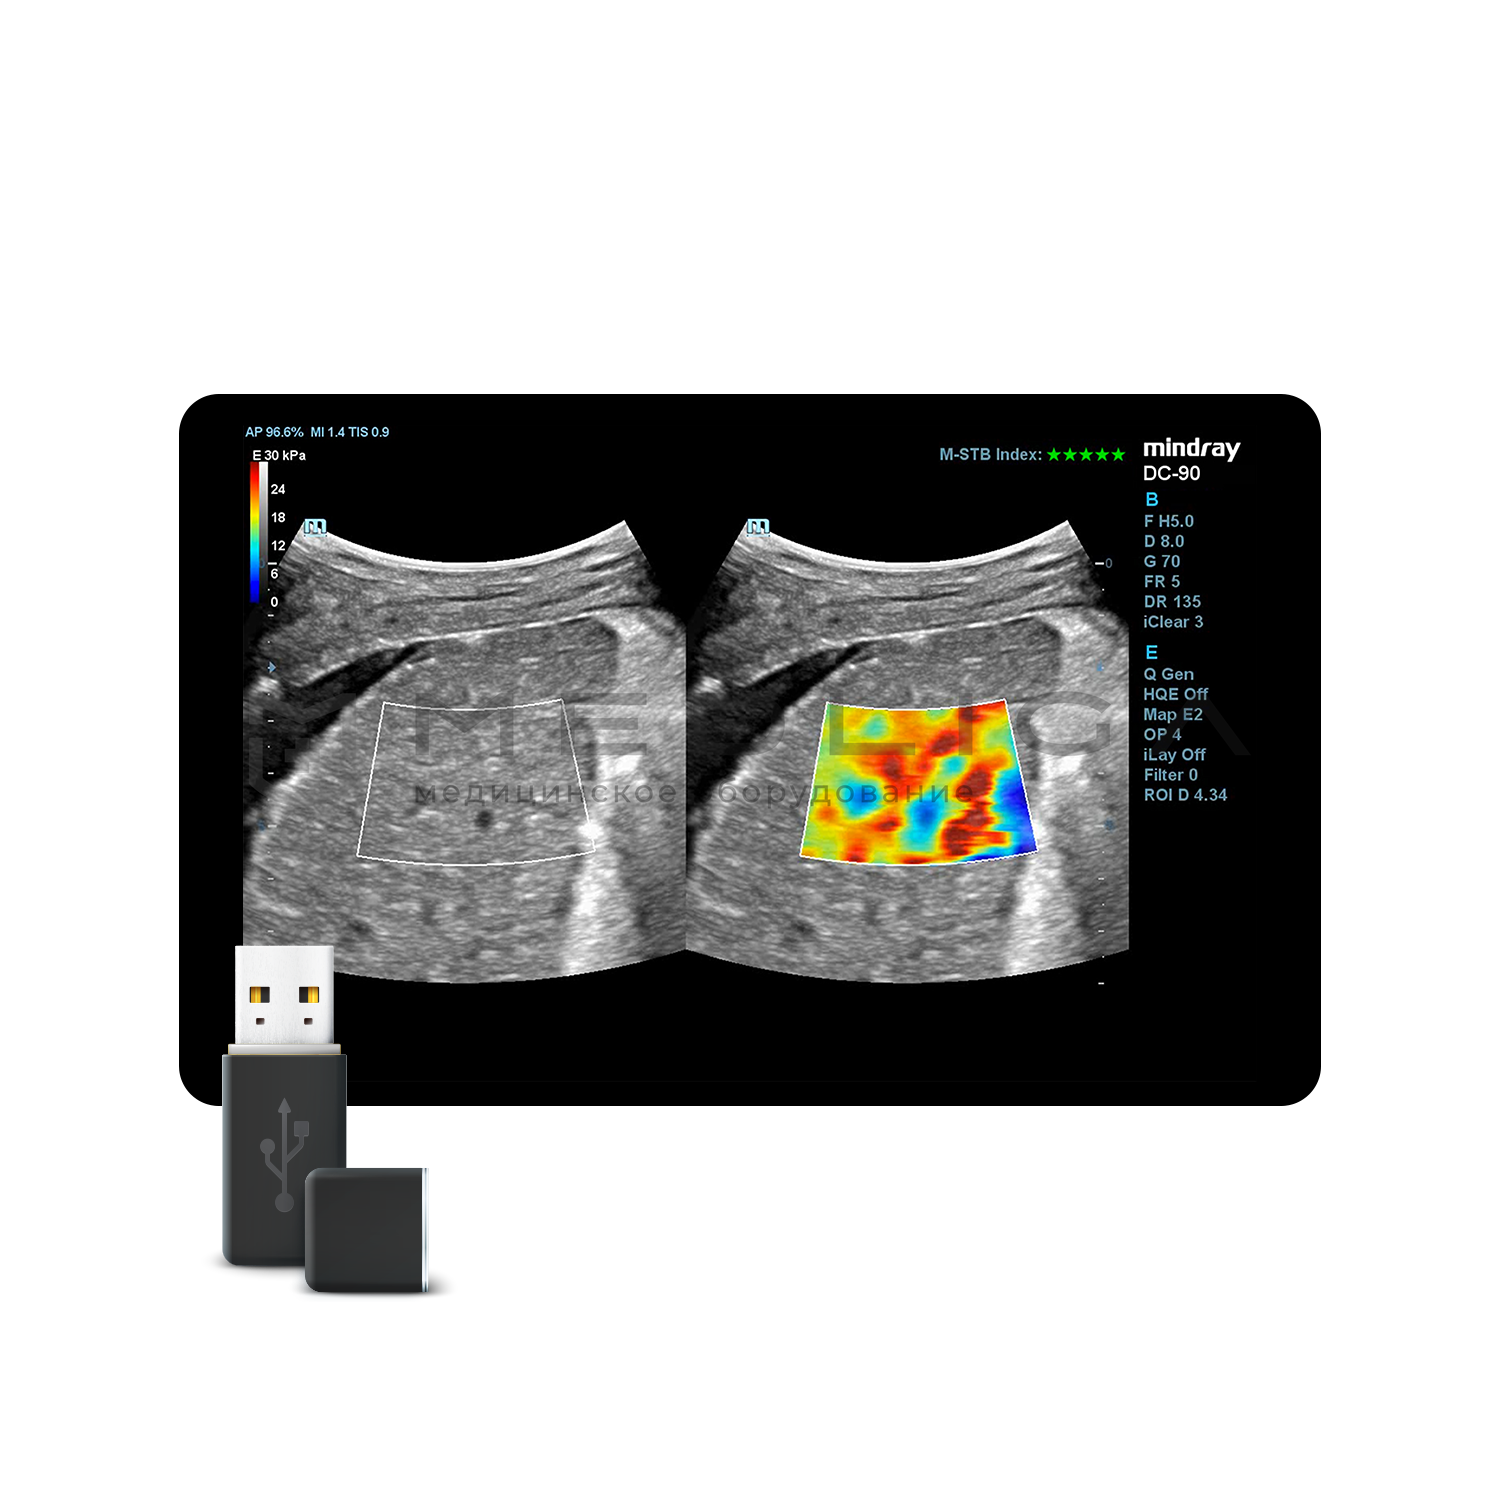

Программное обеспечение для оценки эластичности ткани методом эластографии сдвиговой волны (метод 2D-с формированием двухмерной цветовой эластограммы и количественной оценкой эластичности) на линейных и конвексных датчиках.

STE интегрирована с эксклюзивной технологией Ultra-Wide Beam Tracking от Mindray для двумерной эластографии сдвиговой волной в реальном времени. Специализированные измерительные инструменты позволяют проводить количественный анализ модуля упругости с высокой точностью.